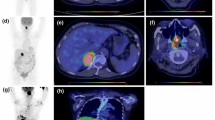

All included patients underwent pretreatment 18F-FDG PET/CT examination. Among them, 63 patients underwent interim PET/CT scans (after 2 to 4 cycles of chemotherapy and/or radiotherapy). Thirty patients underwent end-of-treatment PET/CT scans (after first-line therapy). Interim and end-of-treatment PET/CT scans were carried out 3 weeks after the initial treatment and after the completion of the first-line therapy, respectively.

All patients underwent whole-body (from the skull base to the upper third of the thighs) 18F-FDG PET/CT scans with a dedicated PET/CT system (Discovery VCT; GE Healthcare, Milwaukee, WI). After at least 6 h of fasting with blood glucose level lower than 200 mg/dL, an intravenous injection of 3.7–4.4 MBq/kg 18F-FDG was administered. Approximately 60 min after the injection of 18F-FDG, whole-body CT and PET scans were acquired. Images were corrected for attenuation with low-dose CT data, and corrected PET images were reconstructed using an ordered-subset expectation maximization iterative reconstruction algorithm. The acquired images from CT and PET were reviewed on a dedicated workstation (Xeleris Workstation, GE Healthcare).

PET/CT image analysis

PET/CT images were retrospectively reviewed by two experienced nuclear medicine physicians, who had information on the initial clinical data but were blinded to the reference standard outcome. The pretreatment images were evaluated by SUVmax, which was recorded in regions of interest drawn over all lesions. We selected the highest SUVmax of images identified for each patient. The interim and end-of-treatment PET/CT data were evaluated based on the Deauville score (DS): 1, no uptake above background; 2, uptake ≤ mediastinum; 3, uptake > mediastinum but ≤ liver; 4, uptake moderately stronger than liver; 5, uptake markedly higher than liver and/or the presence of new lesions [15].

Prognostic factors of PFS and OS

In this set of patients, the median SUVmax was 11.4 (range, 1.5–41.4). The optimal SUVmax cut-off value was 9.5 determined by ROC analysis (AUC = 0.698). Using this cut-off value, all patients were divided into high SUVmax (SUVmax ≥9.5, n = 105) and low SUVmax (SUVmax < 9.5, n = 66) groups. A total of 68 (64.8%) patients in the high SUVmax group experienced treatment failure (progression, recurrence or death), whereas 22 (33.3%) patients in the low SUVmax group experienced treatment failure. The Kaplan-Meier survival curves demonstrated that patients in the high SUVmax group had significantly inferior PFS and OS rates (p < 0.001, Fig. 1). The mean PFS and OS in the high SUVmax group were 32.2 ± 2.8 and 43.2 ± 3.0 months, respectively, and those in the low SUVmax group were 54.9 ± 3.7 and 66.0 ± 3.2 months.

In all, 63 patients underwent interim PET/CT, and 21 of them (33.3%) showed a positive PET/CT outcome (scores 4–5). The univariate analysis revealed that patients with scores 1–3 on interim PET/CT were significantly associated with superior survival (PFS, p = 0.003; OS, p = 0.002). Thirty patients underwent end-of-treatment PET/CT after completing their first-line treatment. In accordance with the interim PET/CT outcome, patients with scores of 1–3 on end-of-treatment PET/CT were associated with superior survival (PFS, p < 0.001; OS, p = 0.007).